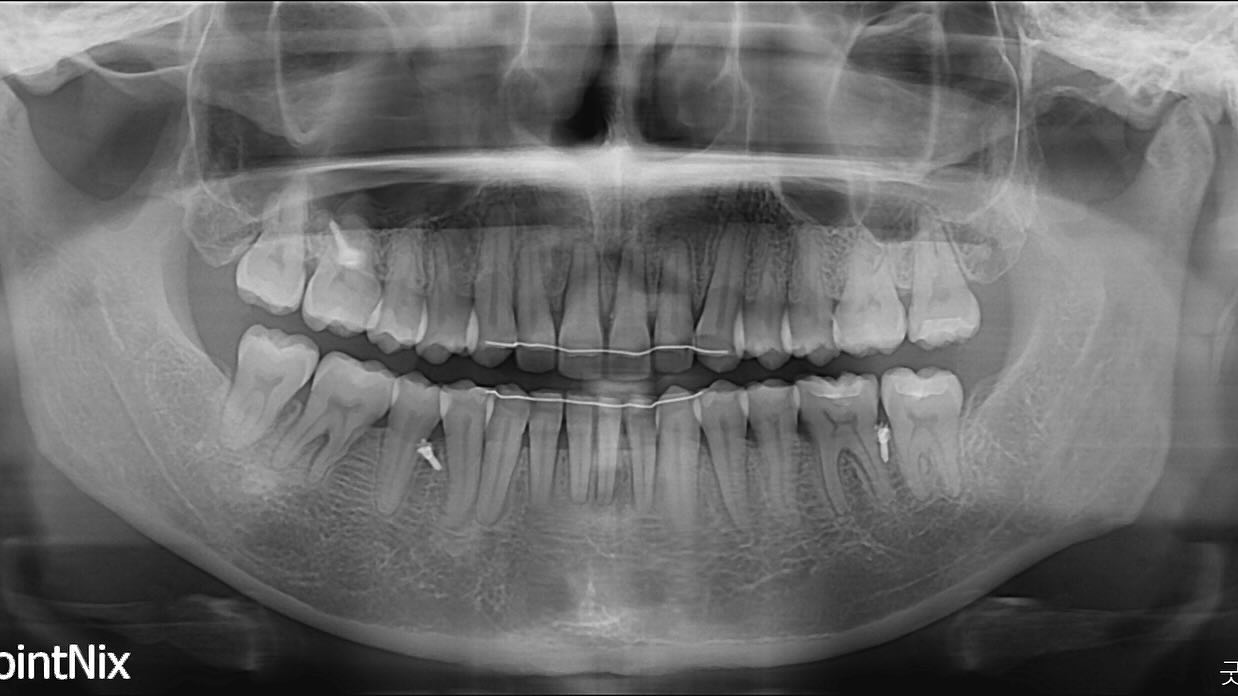

molar protraction

non ext

lip protrusion